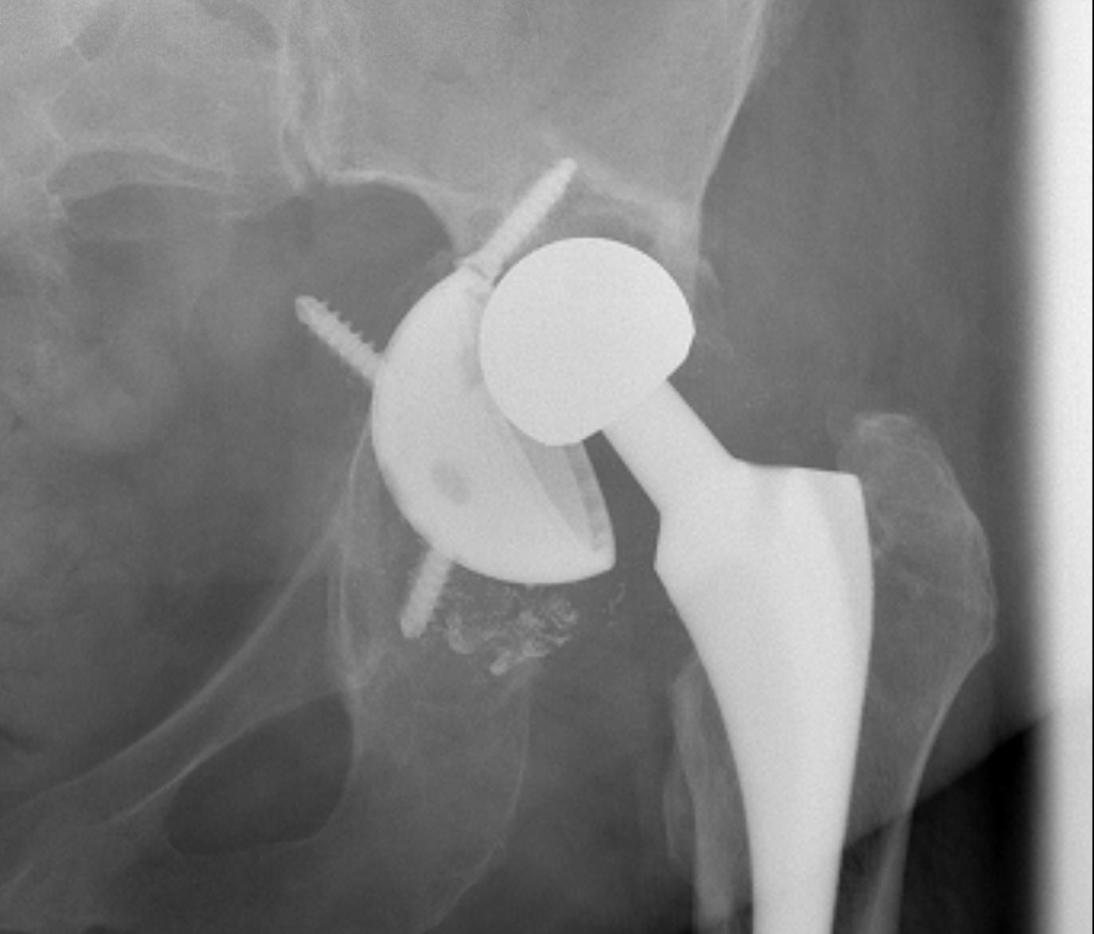

A. Allograft + Antiprotrusio Cages + Cemented Cup

Types

- Ganz / Muller / Burch Schneider

- variations on them

- hook or screws into ilium

- hook or screws onto ischium

- can have extension for screws onto pubis

B. Mesh + Impaction Bone grafting